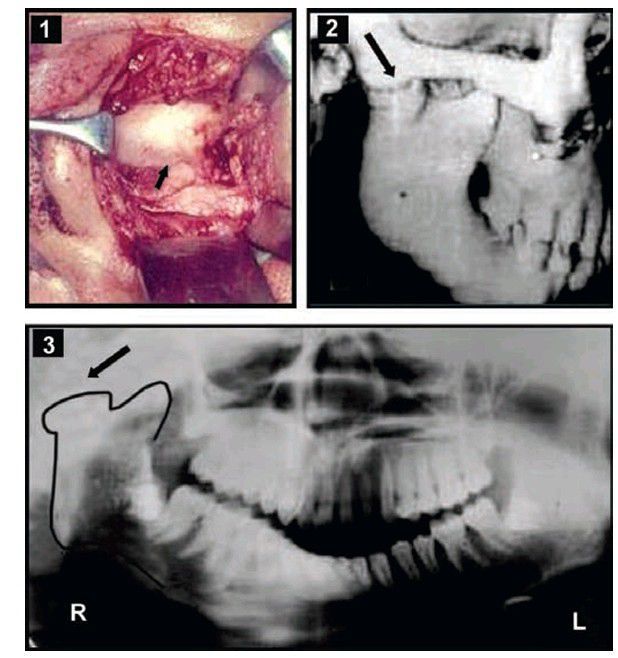

Bony ankylosis: (1) Surgical exposure of (L) TMJ showing the bony ankylosed mass, with deformed head of the condyle, (2) 3D CT scan showing (R) TMJ bony ankylosis, (3) OPG—(R) side. Bony ankylosis